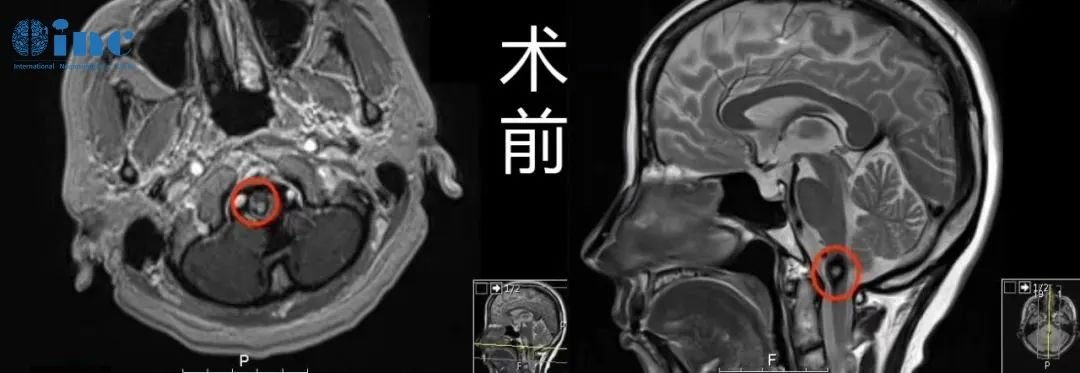

34岁男性-脑干延髓-颈髓室管膜瘤WHO2级

24岁男性-脑干延髓低级别胶质瘤